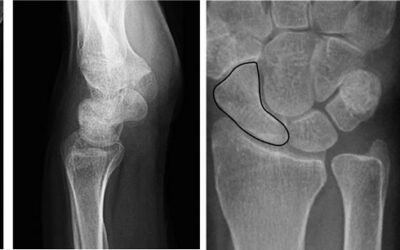

Em 1910, Preiser descreveu a necrose avascular do osso escafóide, que ficou conhecida como Doença de Preiser. Coincidentemente, no mesmo ano, Kienböck descreveu a necrose avascular do osso semilunar, que recebeu o nome de Doença de Kienböck.

Em 1910, Robert Kienböck, radiologista austríaco, descreveu a necrose avascular do osso semilunar, a qual chamou de lunatomalácia.

Coincidentemente, no mesmo ano, Preiser descreveu a necrose avascular do osso escafóide, nomeada Doença de Preiser.